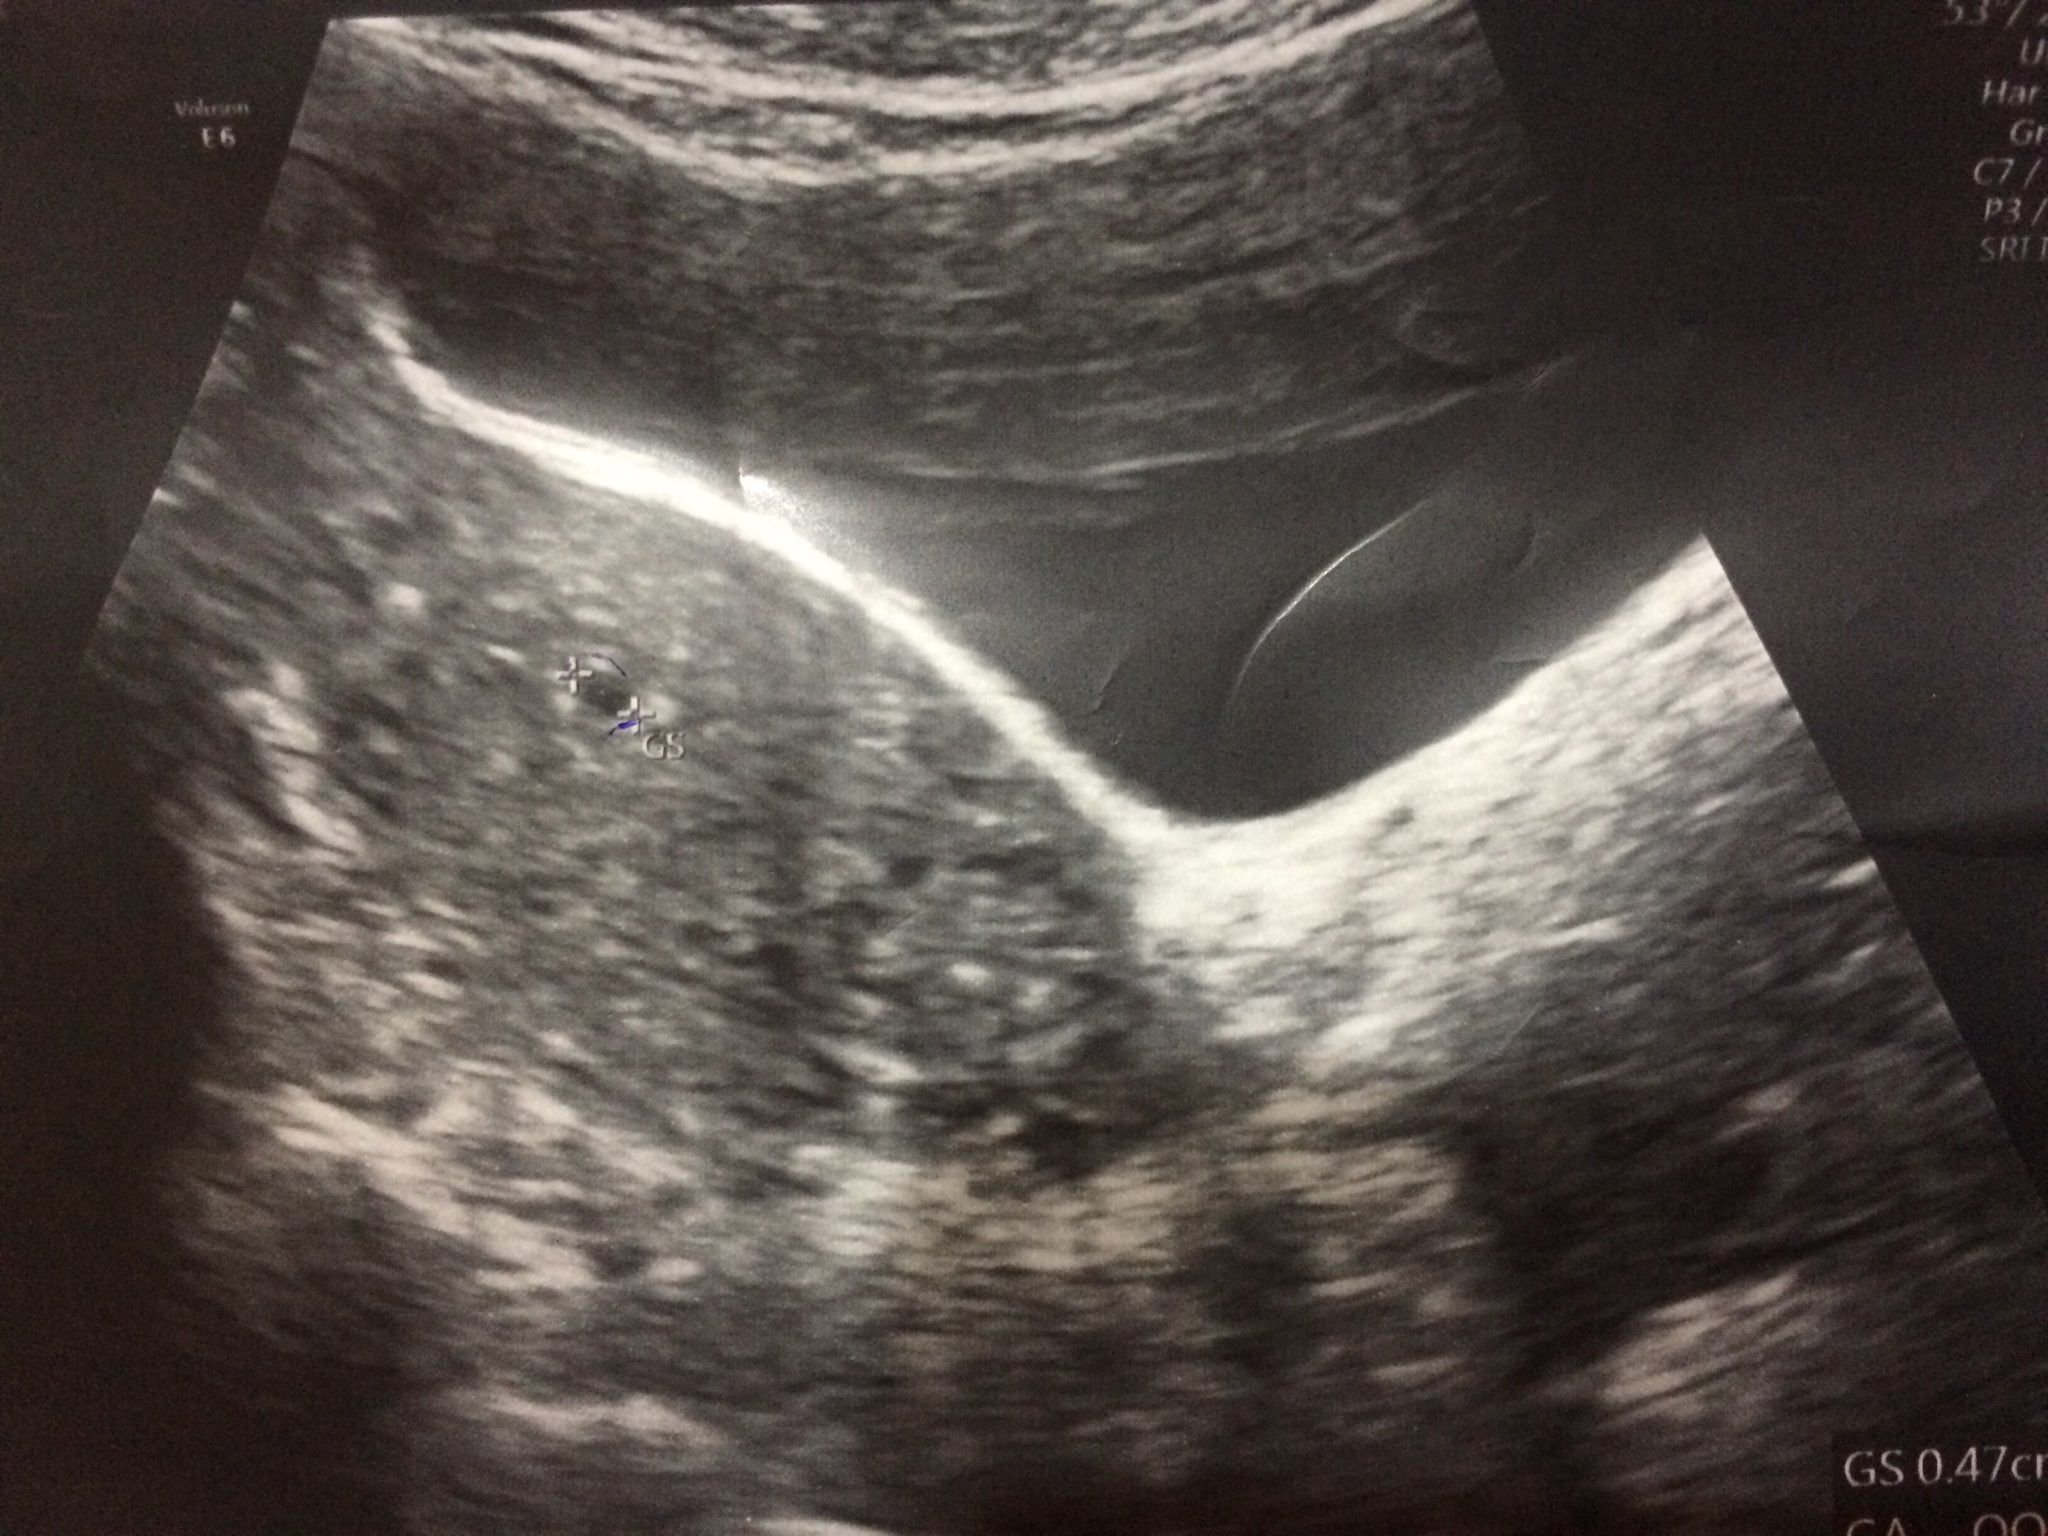

懷孕5週 太小 媽咪愛 育兒問答

懷孕第五周 超音波照寶寶很健康 Samantha Tey的育兒 Blog 隨意窩xuite日誌

懷孕日記 5週 7週 我的懷孕症狀 真的驗到兩條線啦 第一次聽到寶寶心跳 Daphne On Air

孕宝们捉摸不定的胎心胎芽 到底什么时候才会出现

孕囊形状